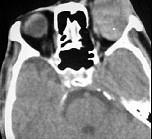

问题 男性45岁,左眼疼痛伴视力下降1个多月,左眼明显外突,CT扫描如图所示,最可能诊断为()

选项 A.左侧眶内炎性假瘤 B.眶内血管瘤 C.眶内纤维瘤 D.眶内结核 E.眶内转移瘤

答案 A